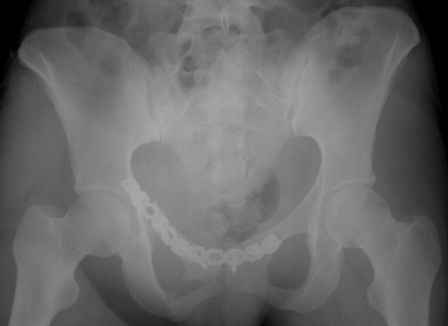

Спасибо за полезные советы! По inlet и outlet обнаружили перелом крестцас той-же стороны. Сегодня прооперировали реконструктивной пластиной с перекрытием симфиза, крестец, увы, фиксировать было нечем - оставили так (тем более, что грубой дислокации там нет). Рентгенограммы выложу позже.

Серия до- и послеоперационных снимков этой пациентки. Хотя бы post factum обсудить. Не знаю, что можно сделать с задними отделами стержневым аппаратом, но три крепких парня открытым путем с помощью "волшебных" слов еле-еле смогли отрепонировать - сзади все было очень ригидно!